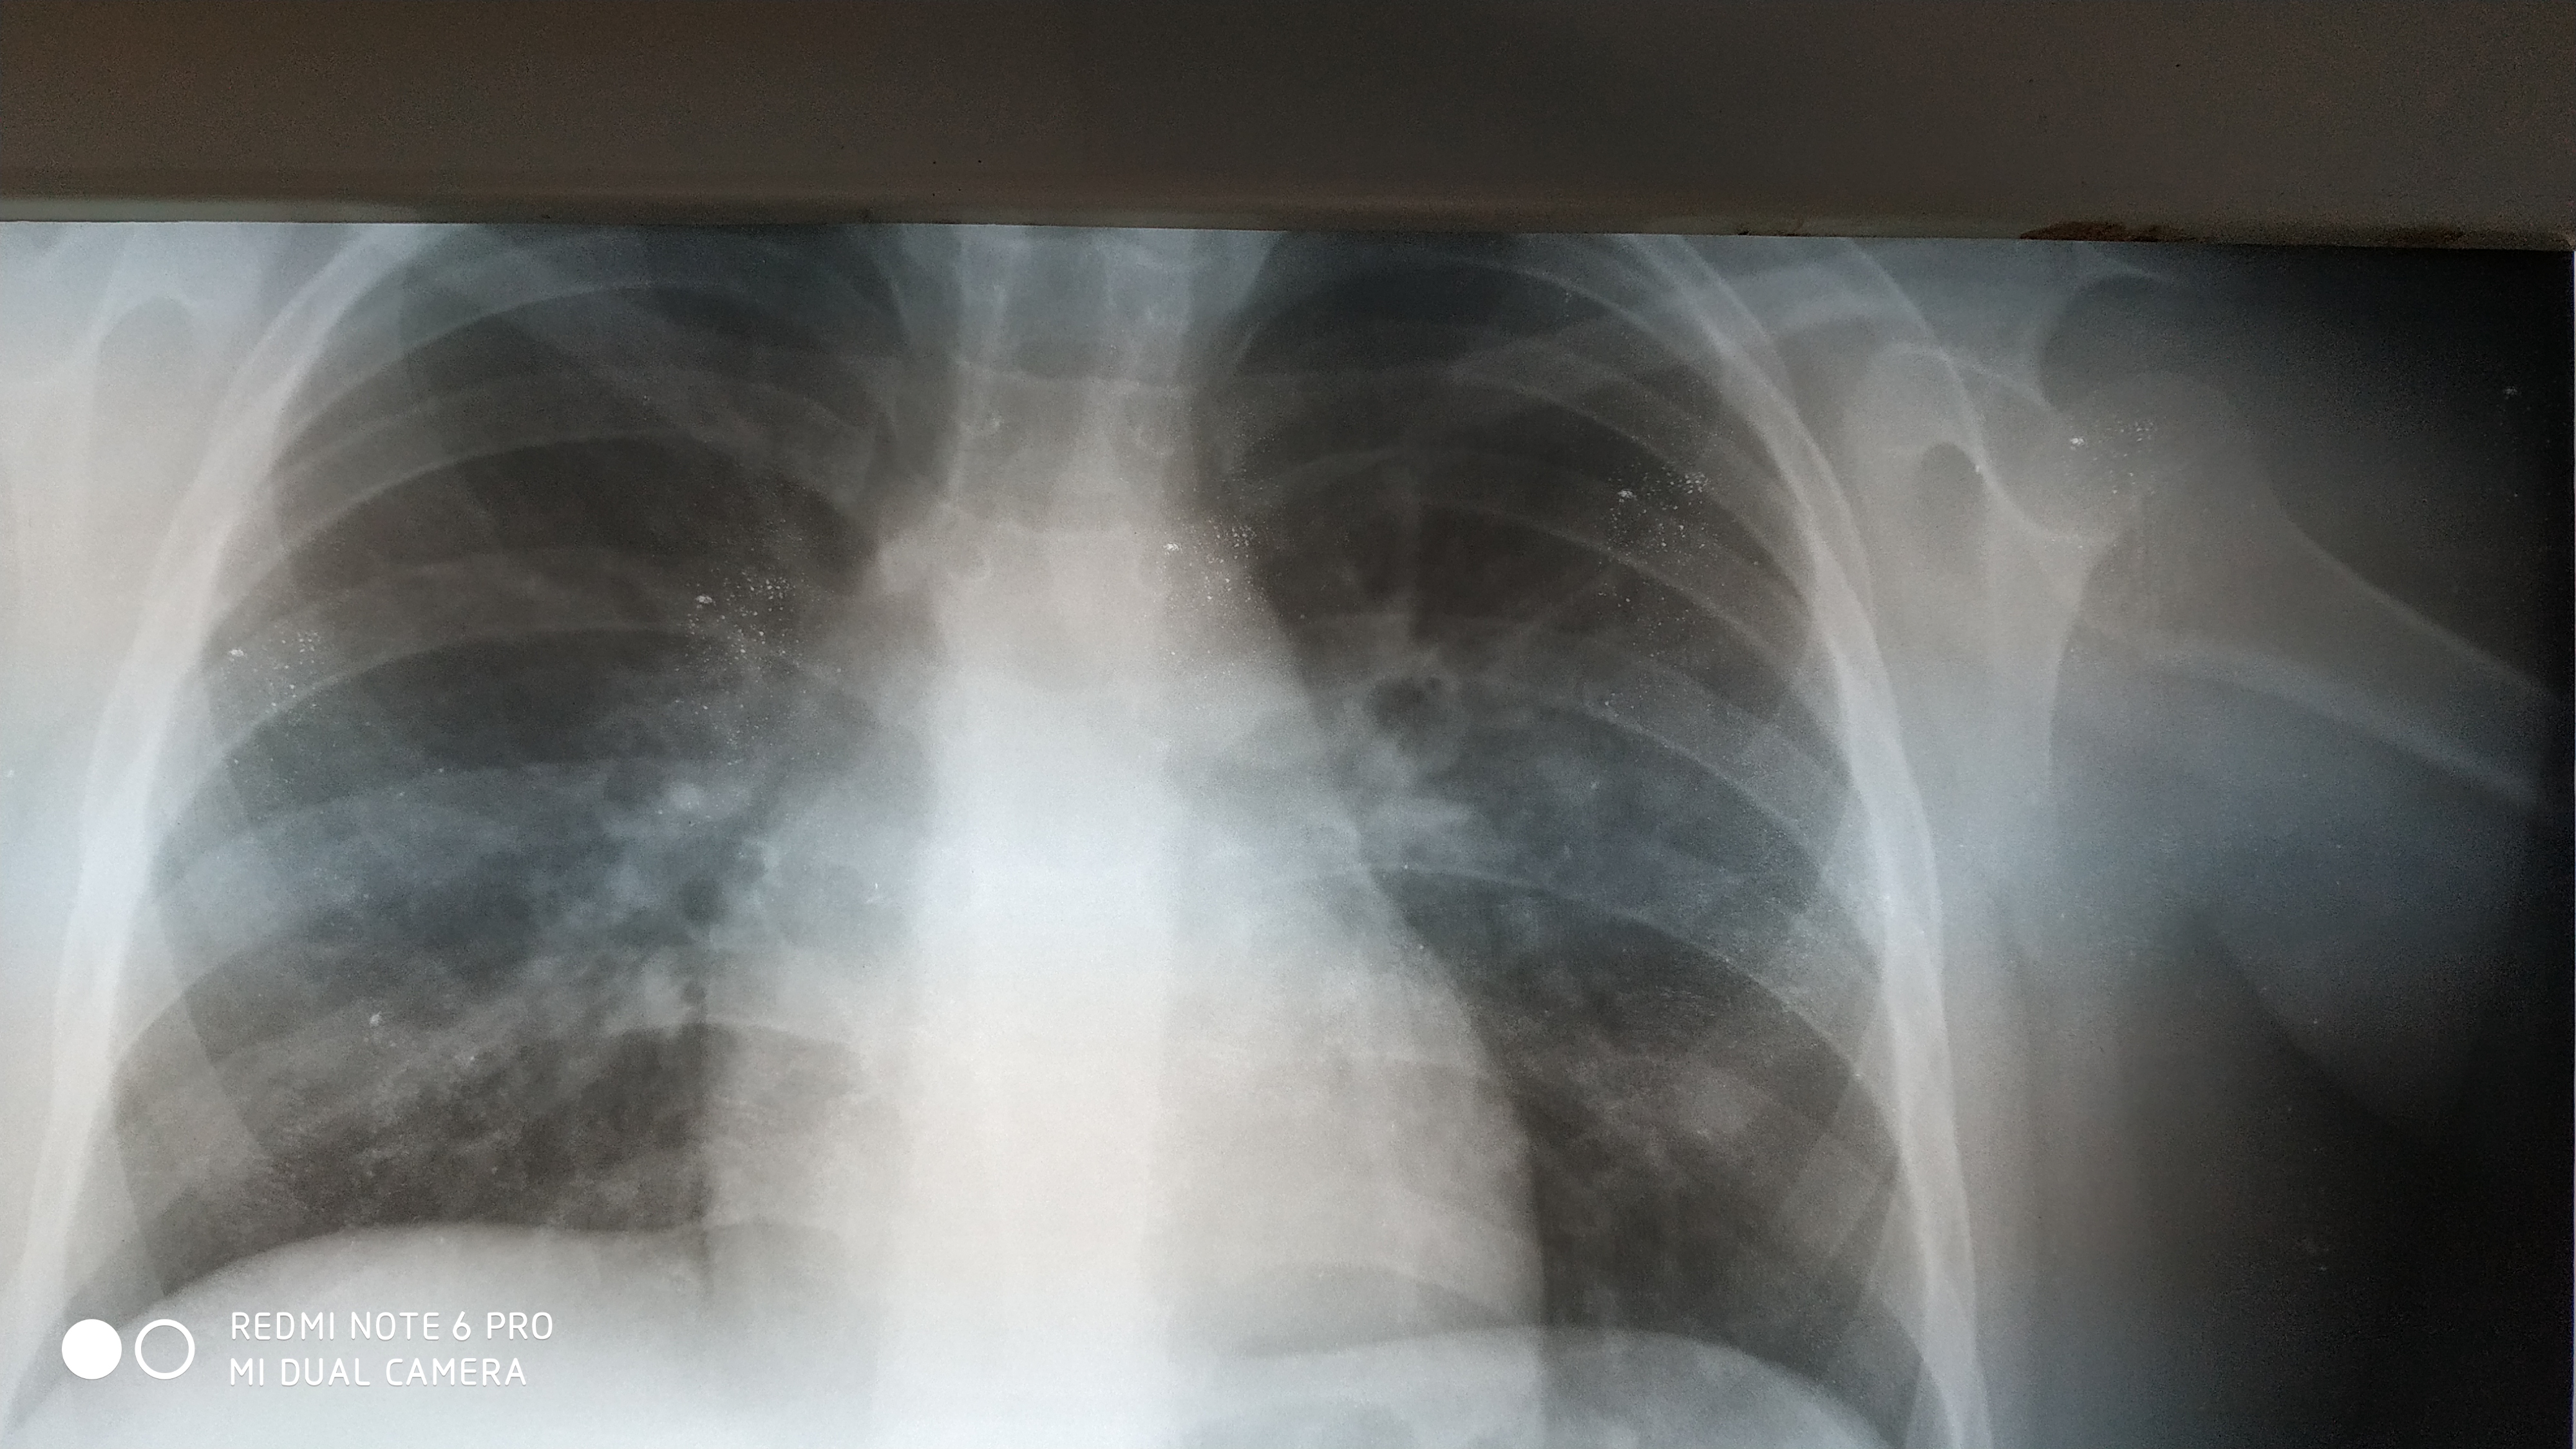

Поражение легких является одним из основных симптомов коронавируса (COVID-19). В данной статье представлены фото рентгеновских снимков, которые позволяют визуально оценить состояние легких при этом заболевании.

Коронавирус пневмония рентген

Рентген легких пневмония коронавирус

На фотографиях рентгеновских снимков видно, как вирус воздействует на легочную ткань. Характерные признаки поражения легких включают пятна, инфильтраты и наличие жидкости внутри легочных альвеол.

Фото рентгеновских снимков помогают врачам и специалистам визуально определить степень поражения легких и принять соответствующие меры лечения и поддержки пациента.